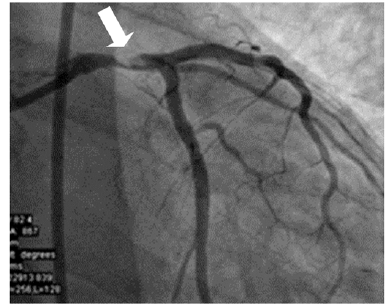

Um paciente de 55 anos de idade, diabético, vem apresentando dor torácica de início recente. São realizados ecocardiograma e cateterismo cardíaco. No ecocardiograma, percebe-se função ventricular conforme a imagem diminuída (40%), com hipocinesia de parede.

Um paciente de 55 anos de idade, diabético, vem apresentando dor torácica de início recente. São realizados ecocardiograma e cateterismo cardíaco. No ecocardiograma, percebe-se função ventricular conforme a imagem diminuída (40%), com hipocinesia de parede.